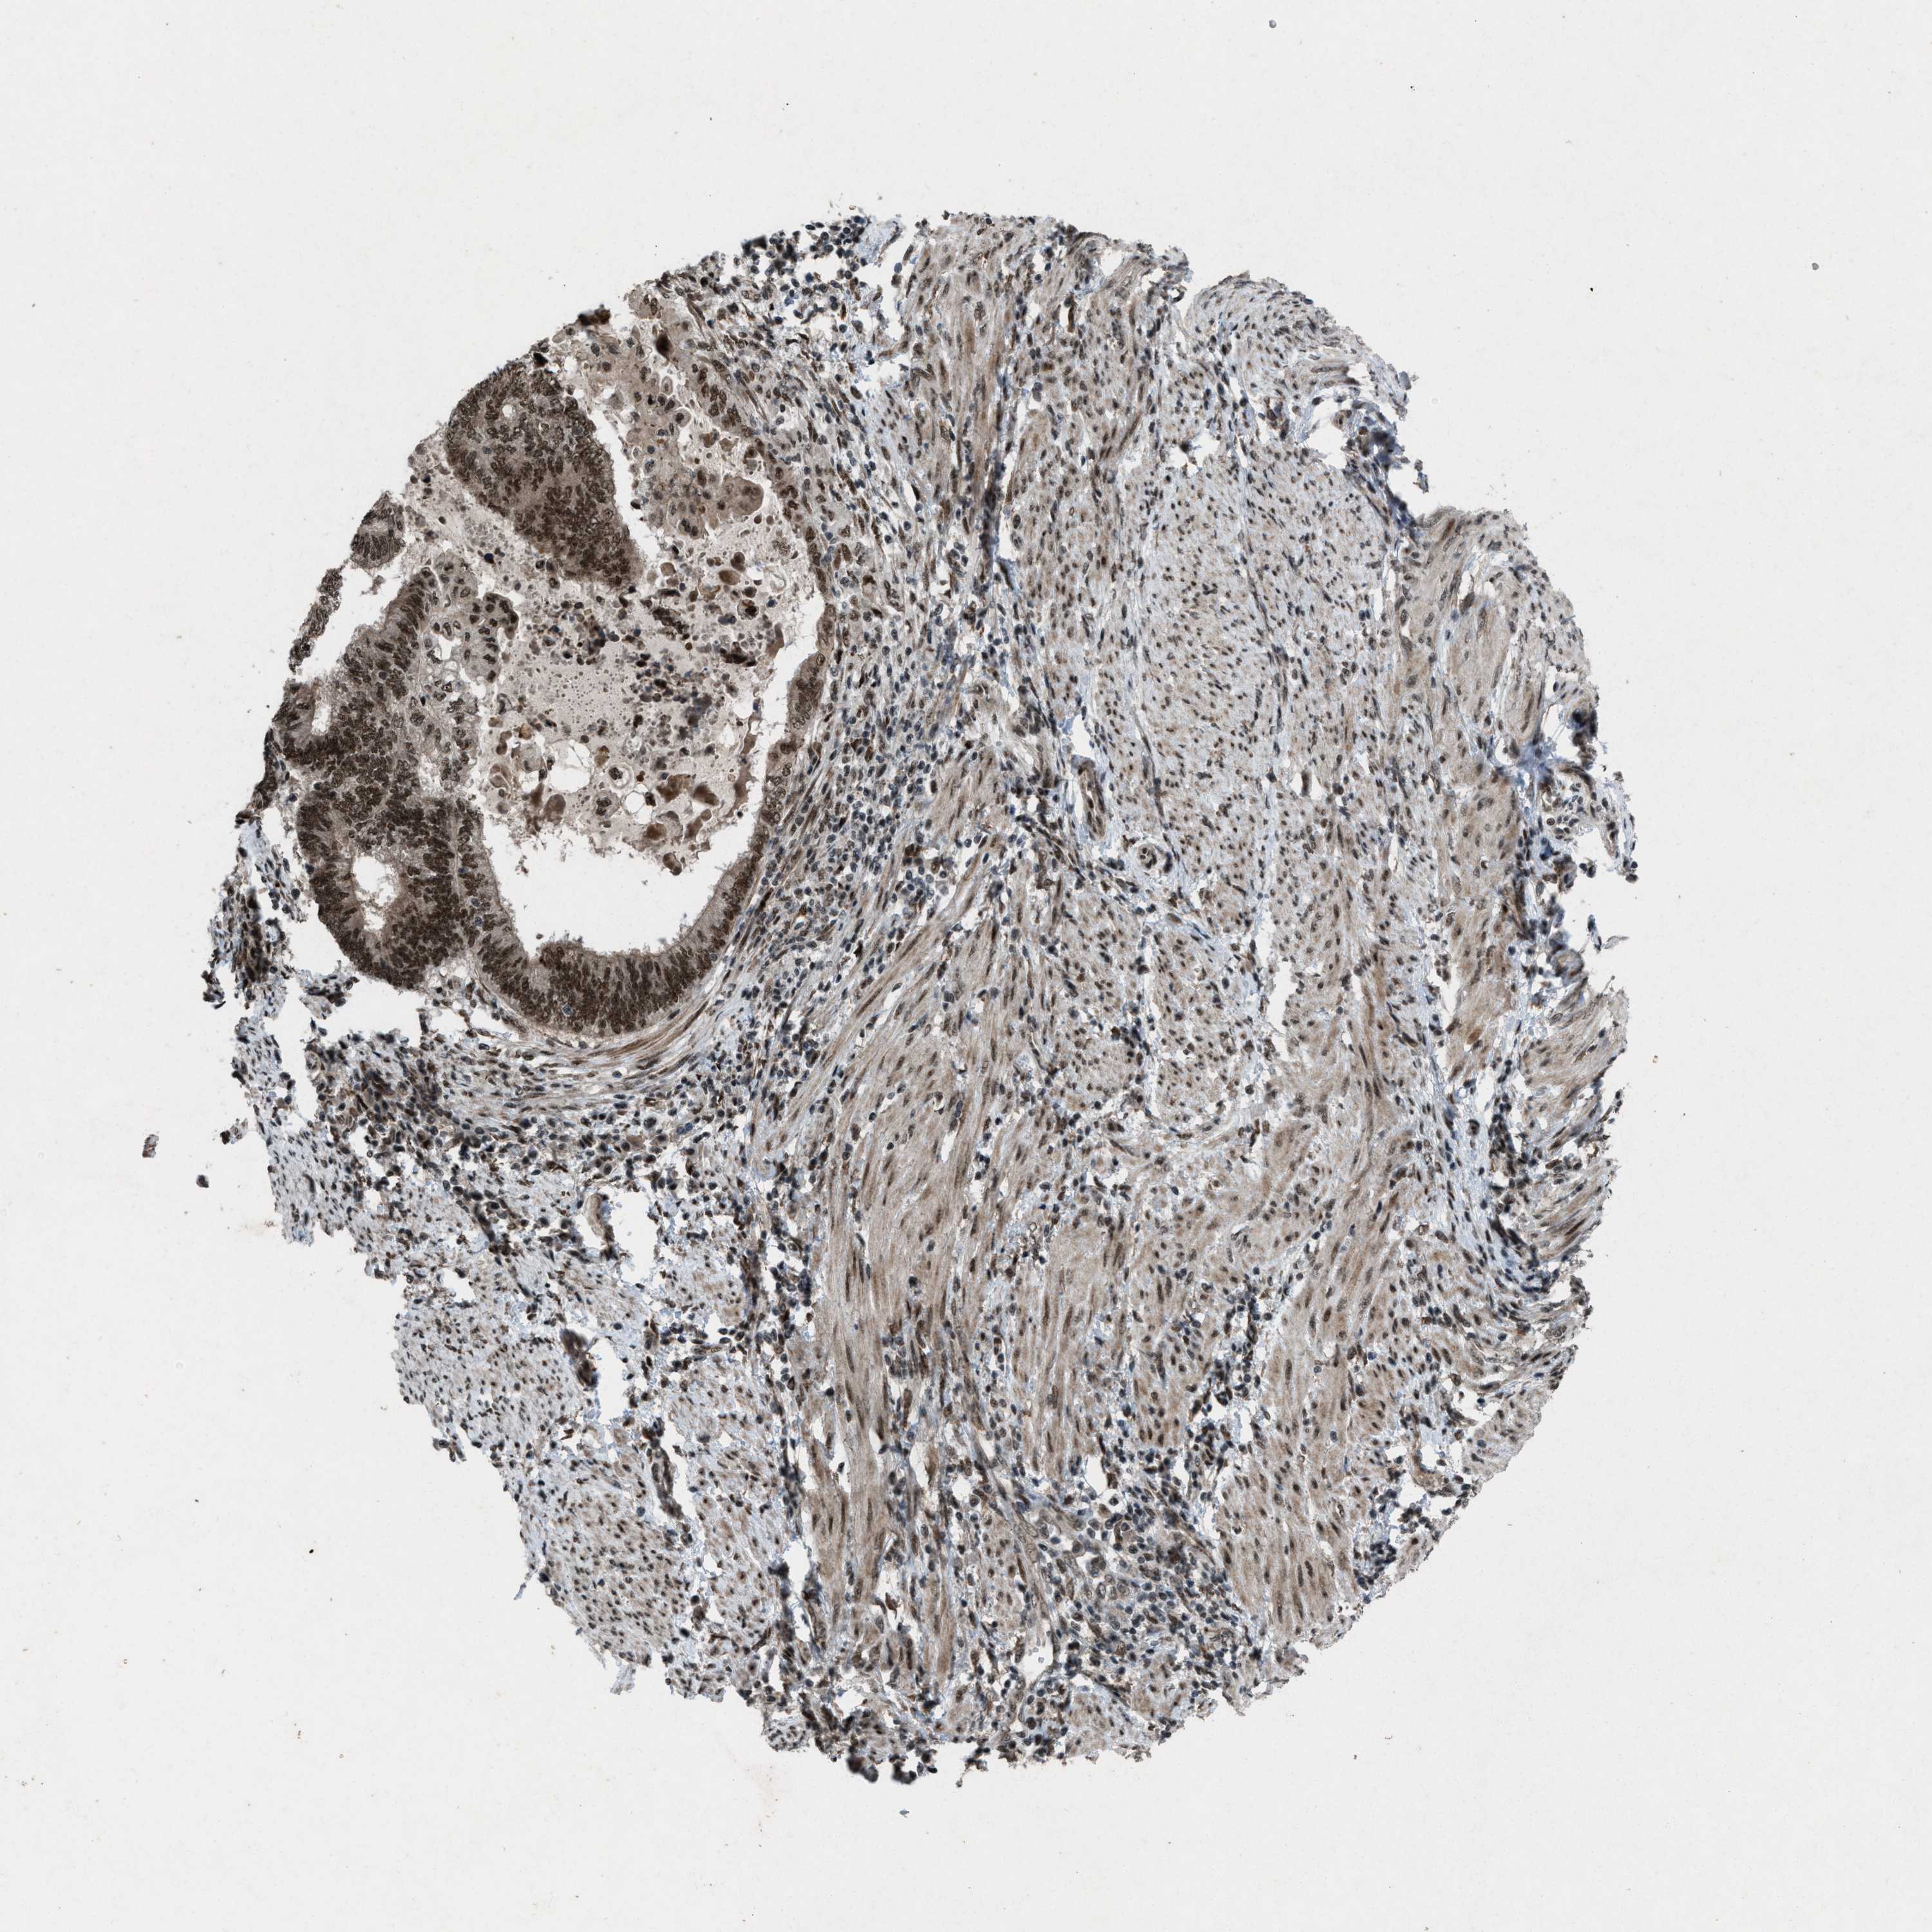

ENDOMETRIAL CANCER - Protein expressioni

A mouse-over function shows sample information and annotation data. Click on an image to view it in a full screen mode. Samples can be filtered based on level of antibody staining by selecting one or several of the following categories: high, medium, low and not detected. The assay and annotation is described here.

Note that samples used for immunohistochemistry by the Human Protein Atlas do not correspond to samples in the TCGA dataset.

Antibody stainingi

Antibody staining in the annotated cell types in the current human tissue is reported as not detected, low, medium, or high, based on conventional immunohistochemistry profiling in selected tissues. This score is based on the combination of the staining intensity and fraction of stained cells.

Each image is clickable and will lead to virtual microscopy that enables deeper exploration of all samples and also displays staining intensity scores, fraction scores and subcellular localization as well as patient and tissue information for each sample.

Antibody HPA021554

Staining

High

Medium

Low

Not detected

Intensity

Strong

Moderate

Weak

Negative

Quantity

>75%

75%-25%

<25%

None

Location

Nuclear

Cytoplasmic/membranous

Cytoplasmic/membranous,nuclear

Adenocarcinoma, NOS

Adenoma, NOS